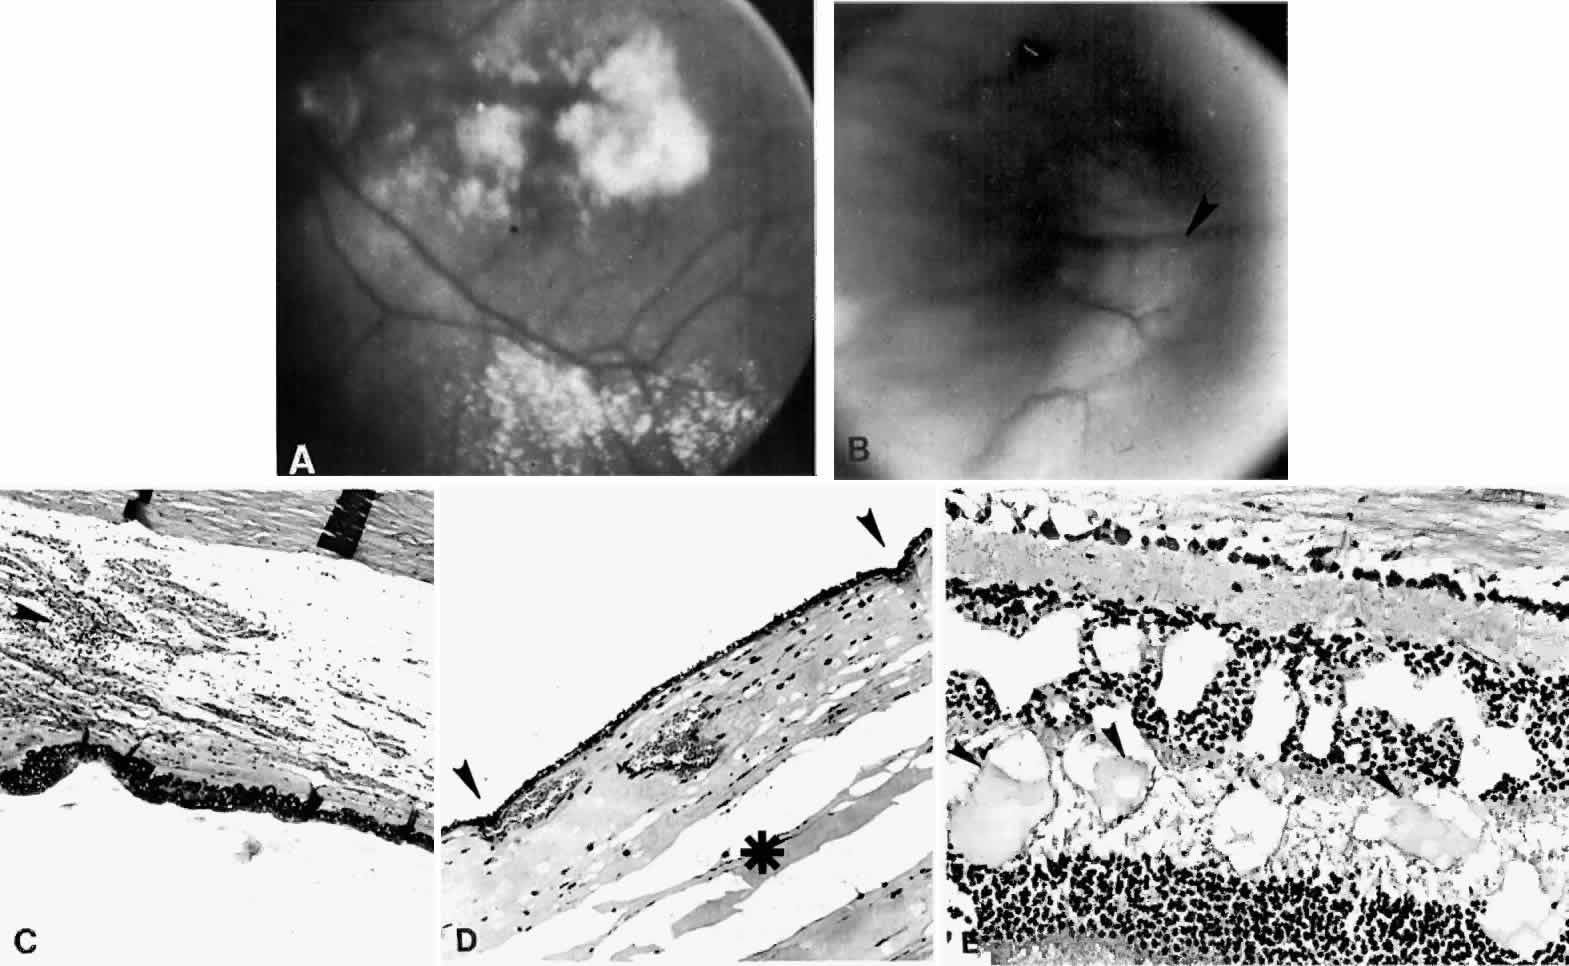

Fig. 8. This choroidal and ciliary body detachment, which occurred after intracapsular cataract extraction, was mistaken for a malignant melanoma.39 A. Iris incarceration in the wound (arrow) and extensive ciliary body effusion consisting of a dense, proteinaceous material (asterisk) (H & E, × 115). B. Effusion of the choroid near the ora serrata by a moderately dense, proteinaceous material without inflammatory cells. Note folds of choroid (arrowheads) (H & E, × 115).

Fig. 9. A. This serosanguineous ciliochoroidal effusion (arrow), which occurred after iridectomy for an iris melanoma in a 68-year-old man, was mistaken for a choroidal melanoma (H & E, × 25). B. Site of the limbal wound (arrowhead) with incarceration of the iris base and residual melanoma in the iris, anterior aspect of the ciliary body, and trabecular meshwork (H & E, × 60).

Fig. 10. A. This extensive ciliochoroidal effusion (asterisk), which occurred 4 years after iridencleisis in a 70-year-old man,39 was mistaken for a malignant melanoma. The iris (arrow) is incarcerated in the limbal wound, and a flat, edematous infiltration bleb (arrowheads) is present (H & E, × 25). B. Area of the ora serrata shows a ciliochoroidal effusion with proteinaceous material separating the tangentially oriented collagen fibers (arrowheads) that connect the choroid and ciliary body to the sclera (H & E, × 115).

Fig. 12. A ciliochoroidal effusion in the eye of a 16-year-old boy, who developed sympathetic uveitis after a corneal laceration. A. Scar of the traumatic corneal perforation, with fibrous tissue ingrowth (asterisk) and adherent lens remnants (arrowhead) (H & E, × 18). B. The appearance of a ciliochoroidal effusion (asterisk) that was first observed in the eye 2 months after corneal perforation and before the development of uveitis in the fellow eye (H & E, × 96). C. The choroid posteriorly is greatly thickened by intense lymphocytic infiltration in which foci of epithelioid cells (arrowheads) display pigment phagocytosis in the absence of necrosis (H & E, × 185).

Fig. 13. A. A ciliochoroidal effusion (asterisk) associated with Toxoplasma retinochoroiditis (H & E, × 50). B. The retina temporally is totally necrotic with encysted T. gondii (H & E, × 25). C. An old chorioretinal scar (arrow) posterior to the area of necrotic retina (H & E, × 160). D. Intense vasculitis and perivascular lymphocytic infiltration of the central vessels in the optic nerve head (H & E, × 185).

Fig. 14. Extensive ciliochoroidal effusion (asterisk) associated with a zonular granulomatous inflammatory infiltration in the episclera (arrowheads) of the eye of a 78-year-old man with rheumatoid arthritis.68 Diffuse, nodular inflammatory infiltrates are present in the markedly edematous ciliary body and choroid. There are several folds of retinal pigment epithelium and inner layers of choroid (arrows) and a flat serous detachment of the retina (H & E, × 40).

Fig. 15. A spontaneous ciliochoroidal effusion was mistaken for a malignant melanoma in a 61-year-old woman who presented with pain, blurred vision, keratitic precipitates, and aqueous cells and flare. A. Gross appearance of the ciliochoroidal effusion (large arrowheads). Small whitish inflammatory nodules are present in the choroid (small arrowheads). The apparent retinal detachment is artifact. B. An extensive ciliochoroidal effusion (asterisk) with a moderately intense chronic inflammatory cellular infiltration. (H & E, × 20). C. The choroid viewed posteriorly, showing occlusive granulomatous vasculitis (arrow) and an intense lymphocytic infiltration crowding the choriocapillaris. The retinal pigment epithelium is intact (H & E, × 290). D. Intense lymphocytic infiltration of choroid, inner scleral lamellae, and episclera (H & E, × 55). E. Diffuse scleritis viewed posteriorly, showing perineural lymphocytic infiltration in the episclera and within a scleral canal (arrowheads) (H & E, × 55).

Fig. 19. A. A ciliochoroidal effusion (asterisk) mistaken for a malignant melanoma and associated with moderately severe panuveitis. A secondary serous retinal detachment (arrowhead) and moderately thickened sclera are evident (H & E, × 15). B. Equatorial choroid with effusion and moderate infiltration of chronic inflammatory cells. Small nodules of proliferated retinal pigment epithelium (arrowheads) and subretinal proteinaceous material (arrow) are shown (H & E, × 80). C. Moderately intense infiltration of plasma cells and some lymphocytes (H & E, × 530). (Courtesy of the Armed Forces Institute of Pathology, Washington, DC)

Fig. 20. A 61-year-old man presented with a 10-day history of decreasing vision in the left eye.96 Examination disclosed a vision of hand motions, an irregularly shallow anterior chamber, closure of the angle, and an intraocular pressure of 45 mmHg. The ora serrata was visible without scleral depression. Ophthalmoscopic examination disclosed two large areas of solid-appearing lesions of the pars plana and anterior choroid (situated superonasally and inferotemporally), detachment of the retina, and a diffuse pigmentary disturbance, which was linear in some areas. Transscleral transillumination disclosed that areas of solid choroidal lesions lit up when viewed through the pupil. Radioactive phosphorus uptake was 16% at 1 hour, 18% at 24 hours, and 44% at 72 hours. The eye was enucleated because of the suspicion of a malignant melanoma. A. An extensive ciliochoroidal effusion (asterisks) showing mild diffuse and marked focal (arrowhead) infiltration of lymphocytes. The equatorial sclera is markedly thickened, and there is a large serous detachment of the retina (H & E, × 17). B. Edematous choroid with a large aggregate of lymphocytes (H & E, × 100). C. The equatorial area shows a thickened sclera, an edematous choroid with diffuse and marked focal aggregates of lymphocytes, localized area of retinal pigment epithelial hypertrophy and hyperplasia (arrowheads), slight folds in the retinal pigment epithelium and inner aspect of the choroid (arrows), and proteinaceous material (asterisk) in the subretinal space (H & E, × 40). D. A choroidal effusion with overlying proliferation of retinal pigment epithelium in nodular and linear configurations. Proteinaceous material is present in some areas in or beneath the retinal pigment epithelium (arrowheads) (H & E, × 180).

Histopathologically, there is a variable lymphocytic infiltrate in the ciliary body and choroid (see Figs. 19 and 20; Fig. 21).96